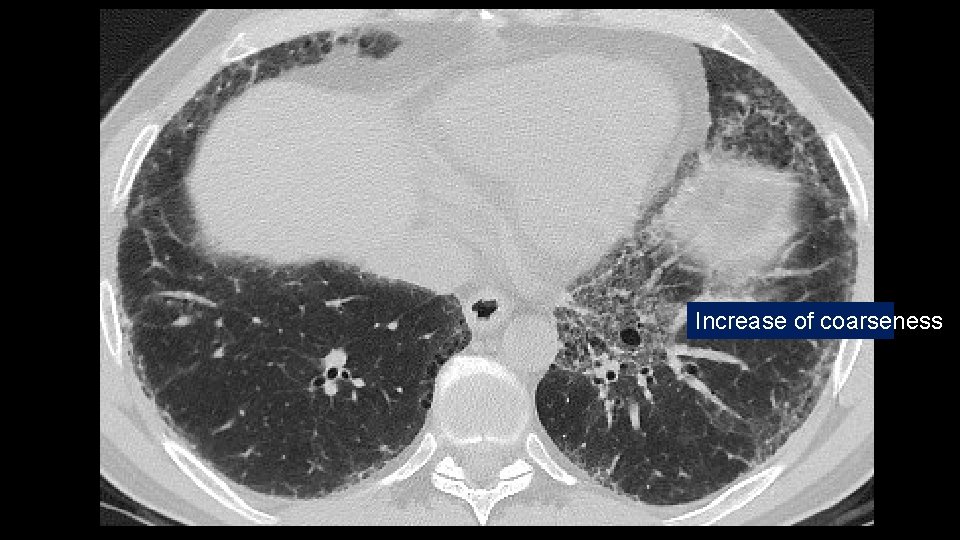

ADDITIONAL HISTORY Patient underwent five cycles of cyclophosphamide (750 mg/mq) EKG and LAB tests: Normal/negative Dyspnea persisted CT scan was repeated seven months later followed by a VATS B

Increase of coarseness

Increase of cysts in the contest of reticulation a ground glass attenuation

Progressive decrease of subpleural sparing

VATS Bx: Fibrosis with honeycombing, in some areas patchy